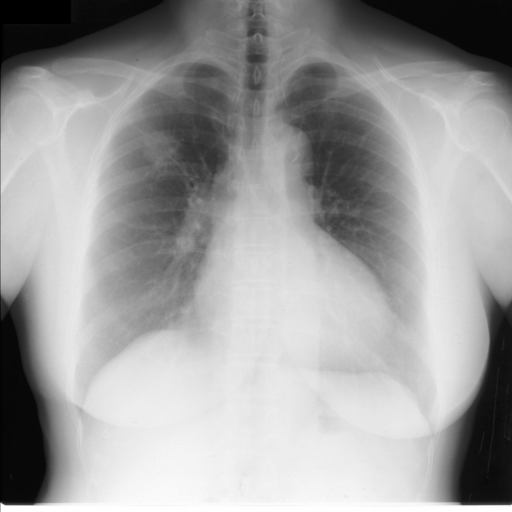

3.1 Dataset

To construct our heart mask and lung mask dataset, we obtained images annotated with heart and lung masks from JSRT dataset [14]. We obtained additional lung masks from Montgomery County X-ray dataset [15] and manually segmented additional heart masks by randomly selecting images with cardiomegaly label and images with cardiomegaly-negative labels from both the NIH Chest X-ray dataset [8] and the CheXpert dataset [16]. After filtering out images with poor quality, our manual segmentation of heart masks yielded additional heart masks. In total, our dataset contains lung masks and heart masks.